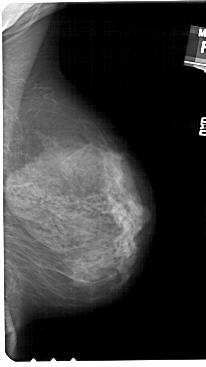

A_1544_1.LEFT_CC

LEFT_CC LINES 4846 PIXELS_PER_LINE 3016 BITS_PER_PIXEL 12 RESOLUTION 43.5 OVERLAY

FILE: A_1544_1.LEFT_CC.OVERLAY

TOTAL_ABNORMALITIES 1

ABNORMALITY 1

LESION_TYPE CALCIFICATION TYPE VASCULAR DISTRIBUTION LINEAR

ASSESSMENT 2

SUBTLETY 2

PATHOLOGY BENIGN

TOTAL_OUTLINES 1

BOUNDARY